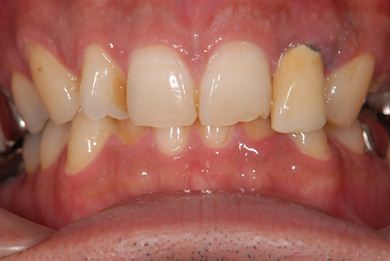

抜歯即日スピードインプラント治療

| 主訴 | 前歯が折れていてないので、インプラント治療を希望。 | ||||||||||||||||||||||||||||||||

| 治療内容 | インプラント1本(抜歯即日スピードインプラント)、ハイブリッドセラミッククラウン1本 | ||||||||||||||||||||||||||||||||